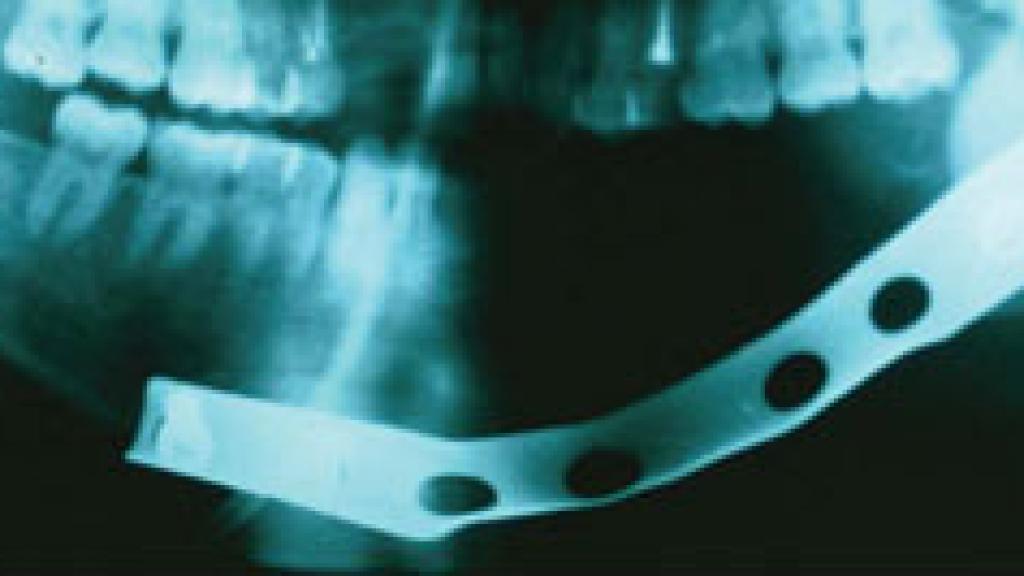

En la intervención, que está previsto se lleve a cabo sobre las 17.00 horas, el cirujano maxilofacial implantará una placa tanto en la parte izquierda como en la derecha de la mandíbula de la víctima, que quedó prácticamente destrozada tras la agresión. Cuando sobre las 03.00 horas del sábado acudió con su familia al hospital, M. apenas podía mover la boca, presentaba un fuerte traumatismo y una hinchazón considerable. Finalmente, cuatro días después de que recibiese el alta, el centro hospitalario notificó a la familia que M. tendría que ser invertenido para reparar los huesos fracturados de su mandíbula.

La recuperación de esta operación, denominada osteosíntesis, durará aproximadamente treinta días, en los que el menor solo podrá ingerir líquidos. Tras esto, los médicos valoraran si las placas de titanio han consolidado la fractura. De ser así, finalmente le volverán a intervenir para retirárselas.

Reconstrucción de mandíbula con placas.